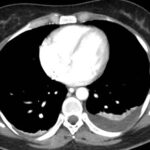

Tomografía de abdomen y pelvis con cte ev: del 13/10/2023.

Complicaciones posquirúrgicas

Tomografía de abdomen con cte ev: del 20/10/2023.

Tomografía de abdomen con cte ev: del 26/10/2023.